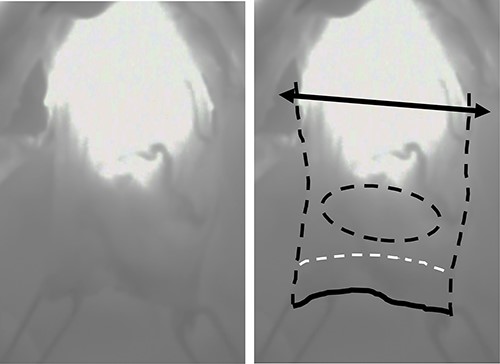

Under upper midline laparotomy, the abdominal part of the gastric tube was mobilized along with the RGEA and RGA after careful dissection. The first and second branches of the RGEA and RGA were divided along the gastric wall, carefully preserving the main vessels. Supra-duodenal arteries were also divided. Then, the anal side margin was set at 1 cm from the distal side of the pylorus, and the duodenum was divided using a linear stapler (Fig. 3A). Before setting the proximal surgical margin, blood supply in the gastric tube was assessed by ICG fluorescence [5]. The visualized ICG fluorescence demonstrated an irregular demarcation line at the distal side of the preserved gastric tube, indicating insufficient blood supply at the greater and lesser curvature compared with the center of the gastric wall (Fig. 4). The gastric tube was thus divided at 2 cm on the oral side from the proximal margin of the tumor, confirming complete removal of the ischemic area. Then gastro-jejunostomy was performed for Roux-en-Y reconstruction (Fig. 3B).

Intraoperative visualization of the blood flow in the proximal side of the gastric tube using ICG fluorescence; bilateral arrow: dissection line of the proximal margin; black dotted line: outline of the proximal part of the gastric tube; black solid line: distal surgical margin; white dotted line: pylorus; black dotted circle: location of the tumor.